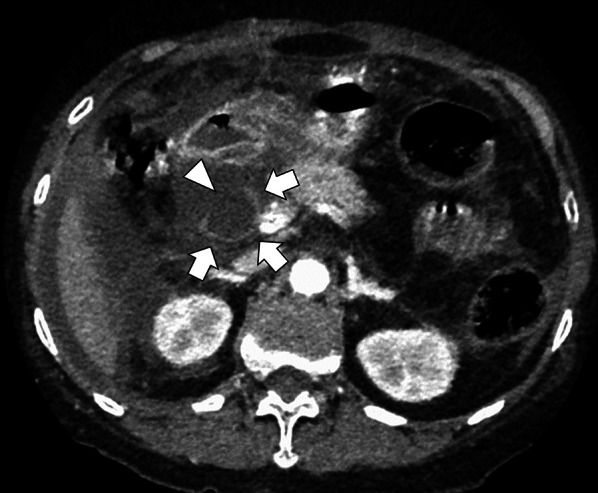

She had no history of past abdominal operations, and other past medical history included choledocholithiasis and pancreatitis. Hematological investigations on admission revealed coagulopathy, renal dysfunction, and circulatory insufficiency (Table 1), which indicated septic disseminated intravascular coagulation. Significantly high levels of serum transaminases, bilirubin, and pancreatic enzymes suggested a condition associated with biliary tract disease. As shown in Fig. 1, enhanced CT revealed that the supraduodenal CBD was markedly dilated similar to a diverticulum (arrow), and the bile duct wall had a partial defect in continuity (arrowhead). Moreover, the common channel of the pancreaticobiliary duct was long at 9.3 mm in length and seemed to be joined outside the muscular layer of the duodenal papilla (arrow) on the coronal CT view (Fig. 2). Eventually, we diagnosed biliary panperitonitis due to the spontaneous CBD perforation accompanied with congenital biliary dilatation and pancreaticobiliary maljunction. As her general condition improved following adequate primary resuscitation, she was able to undergo an emergency laparotomy to cure her septic peritonitis.